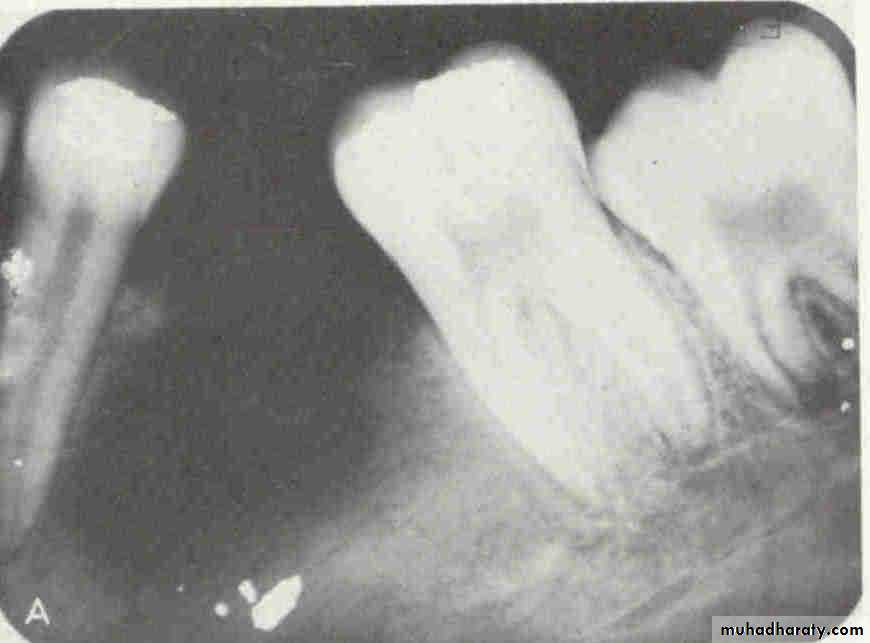

• 2.Position in the jaws:

• - Epicenter coronal to tooth- odontogenic epithelium.

• - Epicenter of the lesion is above the mandibular canal-odontogenic in origin .

• - Epicenter -below lDC- non odontogenic

Cystic ameloblastoma displaced IDC (odontogenic origin)

Epicenter coronal to tooth(odontogenic epithelium )